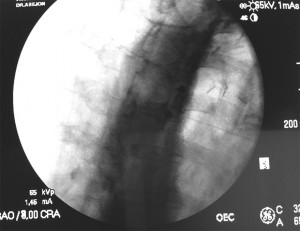

Con el paciente en decúbito prono se coloca una almohada bajo el abdomen. Puntos de referencia con el arco de fluoroscopia en AP se traza un triangulo cuya base está a nivel de L3-L4 con 7.5cm a cada lado y el vértice en la apófisis espinosa de L1. Las agujas se introducen a ambos vértices de la base del triangulo con angulación de 45º en dirección craneal hasta hacer contacto con el cuerpo vertebral de L1, después se aumenta la inclinación hasta 60º para atravesar tangencialmente el cuerpo vertebral hasta llegar al borde anterior del mismo, comprobándolo con el arco de fluoroscopia en lateral. Se inyecta contraste radiopaco (5ml) para ver la localización y difusión del contraste.